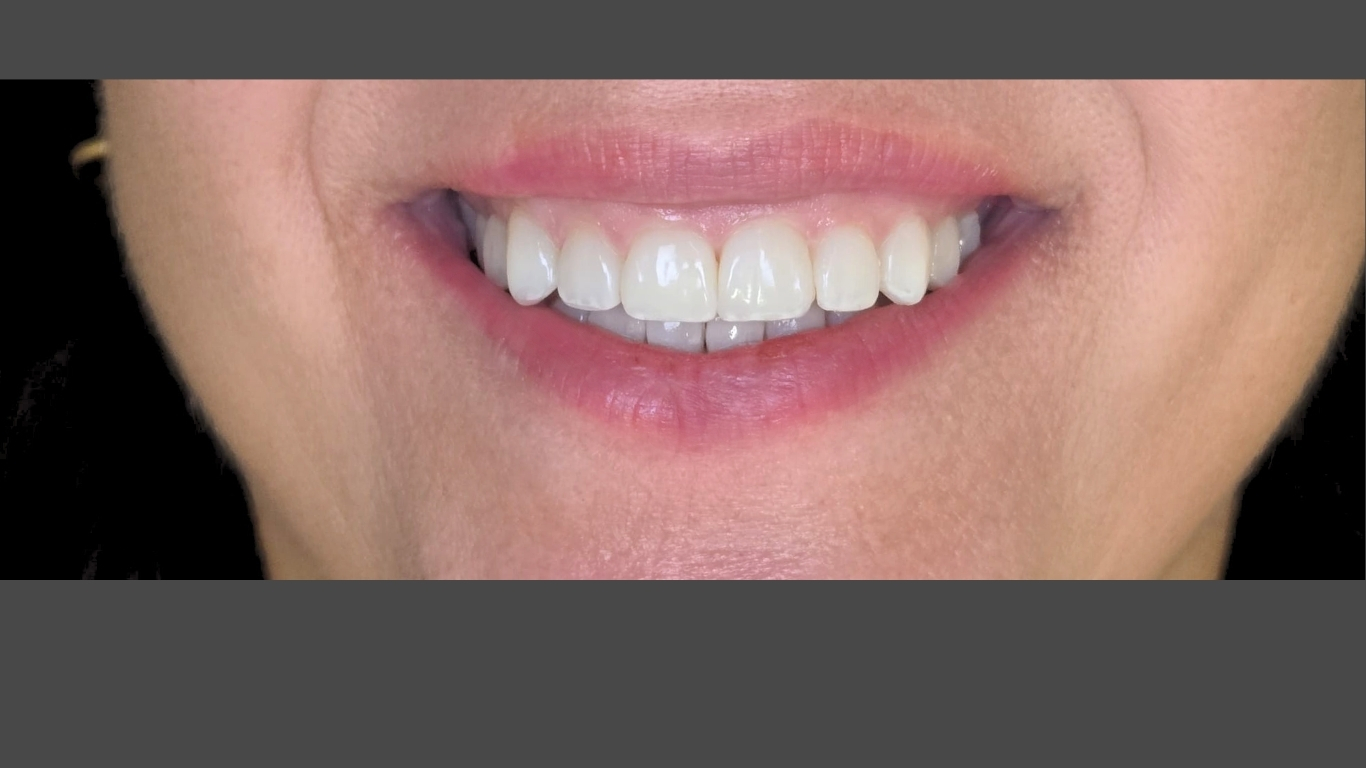

Caso Clínico 1